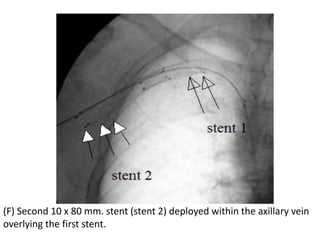

(F) Second 10 x 80 mm. stent (stent 2) deployed within the axillary vein

overlying the first stent.

(E) Angiogram wasdone after deploying the stent, and showed partial opening of the central vein. Decision was done to put another stent in the axillary vein overlapping the proximal stent because there were some clots in that area.

(F) Second 10x 80 mm. stent (stent 2) deployed within the axillary vein overlying the first stent.